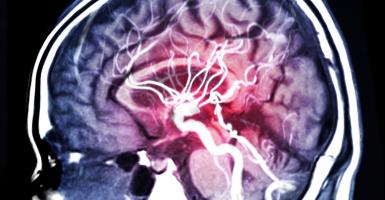

L’IRM arrive au chevet du patient